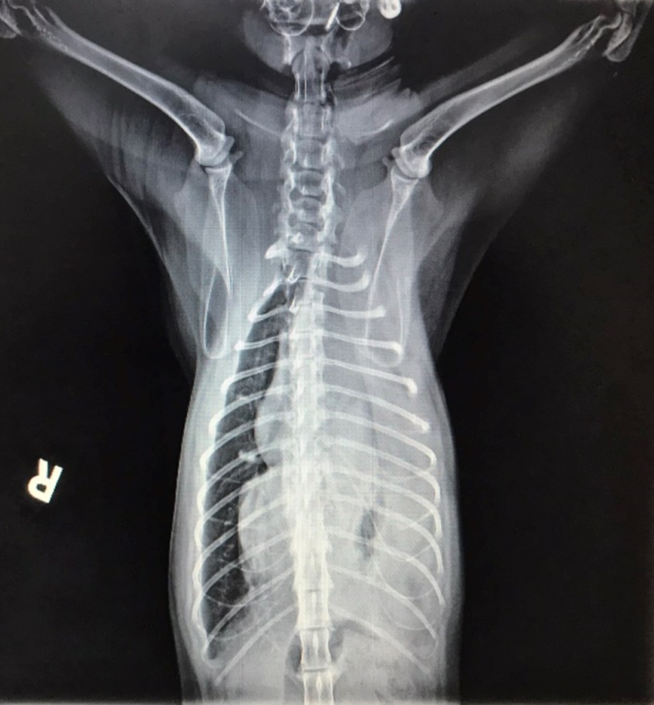

X光下,橫膈分界消失,左側胸腔有不正常軟組織影像

手術後X光,胸腔內異常軟組織影像已經消失

橫膈的邊緣又出現,胸腹腔有完整分界